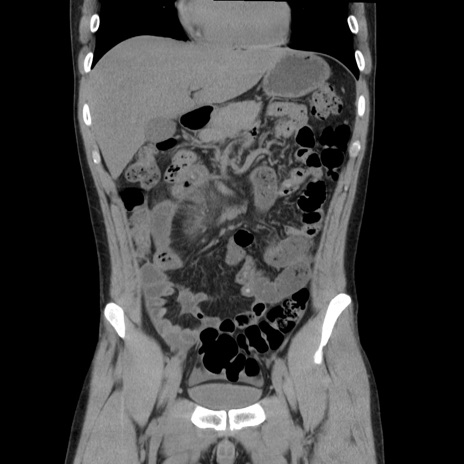

症例36(冠状断像)

【症例】20歳代 男性

【主訴】心窩部痛

【現病歴】今朝より上腹部痛あり。一旦軽快していたが再度出現したため救急要請。昨日夕に白身の魚を含む刺身を食べた。

【身体所見】BP 136/89mmHg、HR 74/min、BT 37.0℃、腹部:膨満、軟、心窩部に圧痛あり。反跳痛なし、筋性防御なし、腸雑音やや亢進あり。

【データ】WBC 17700、CRP 0.48